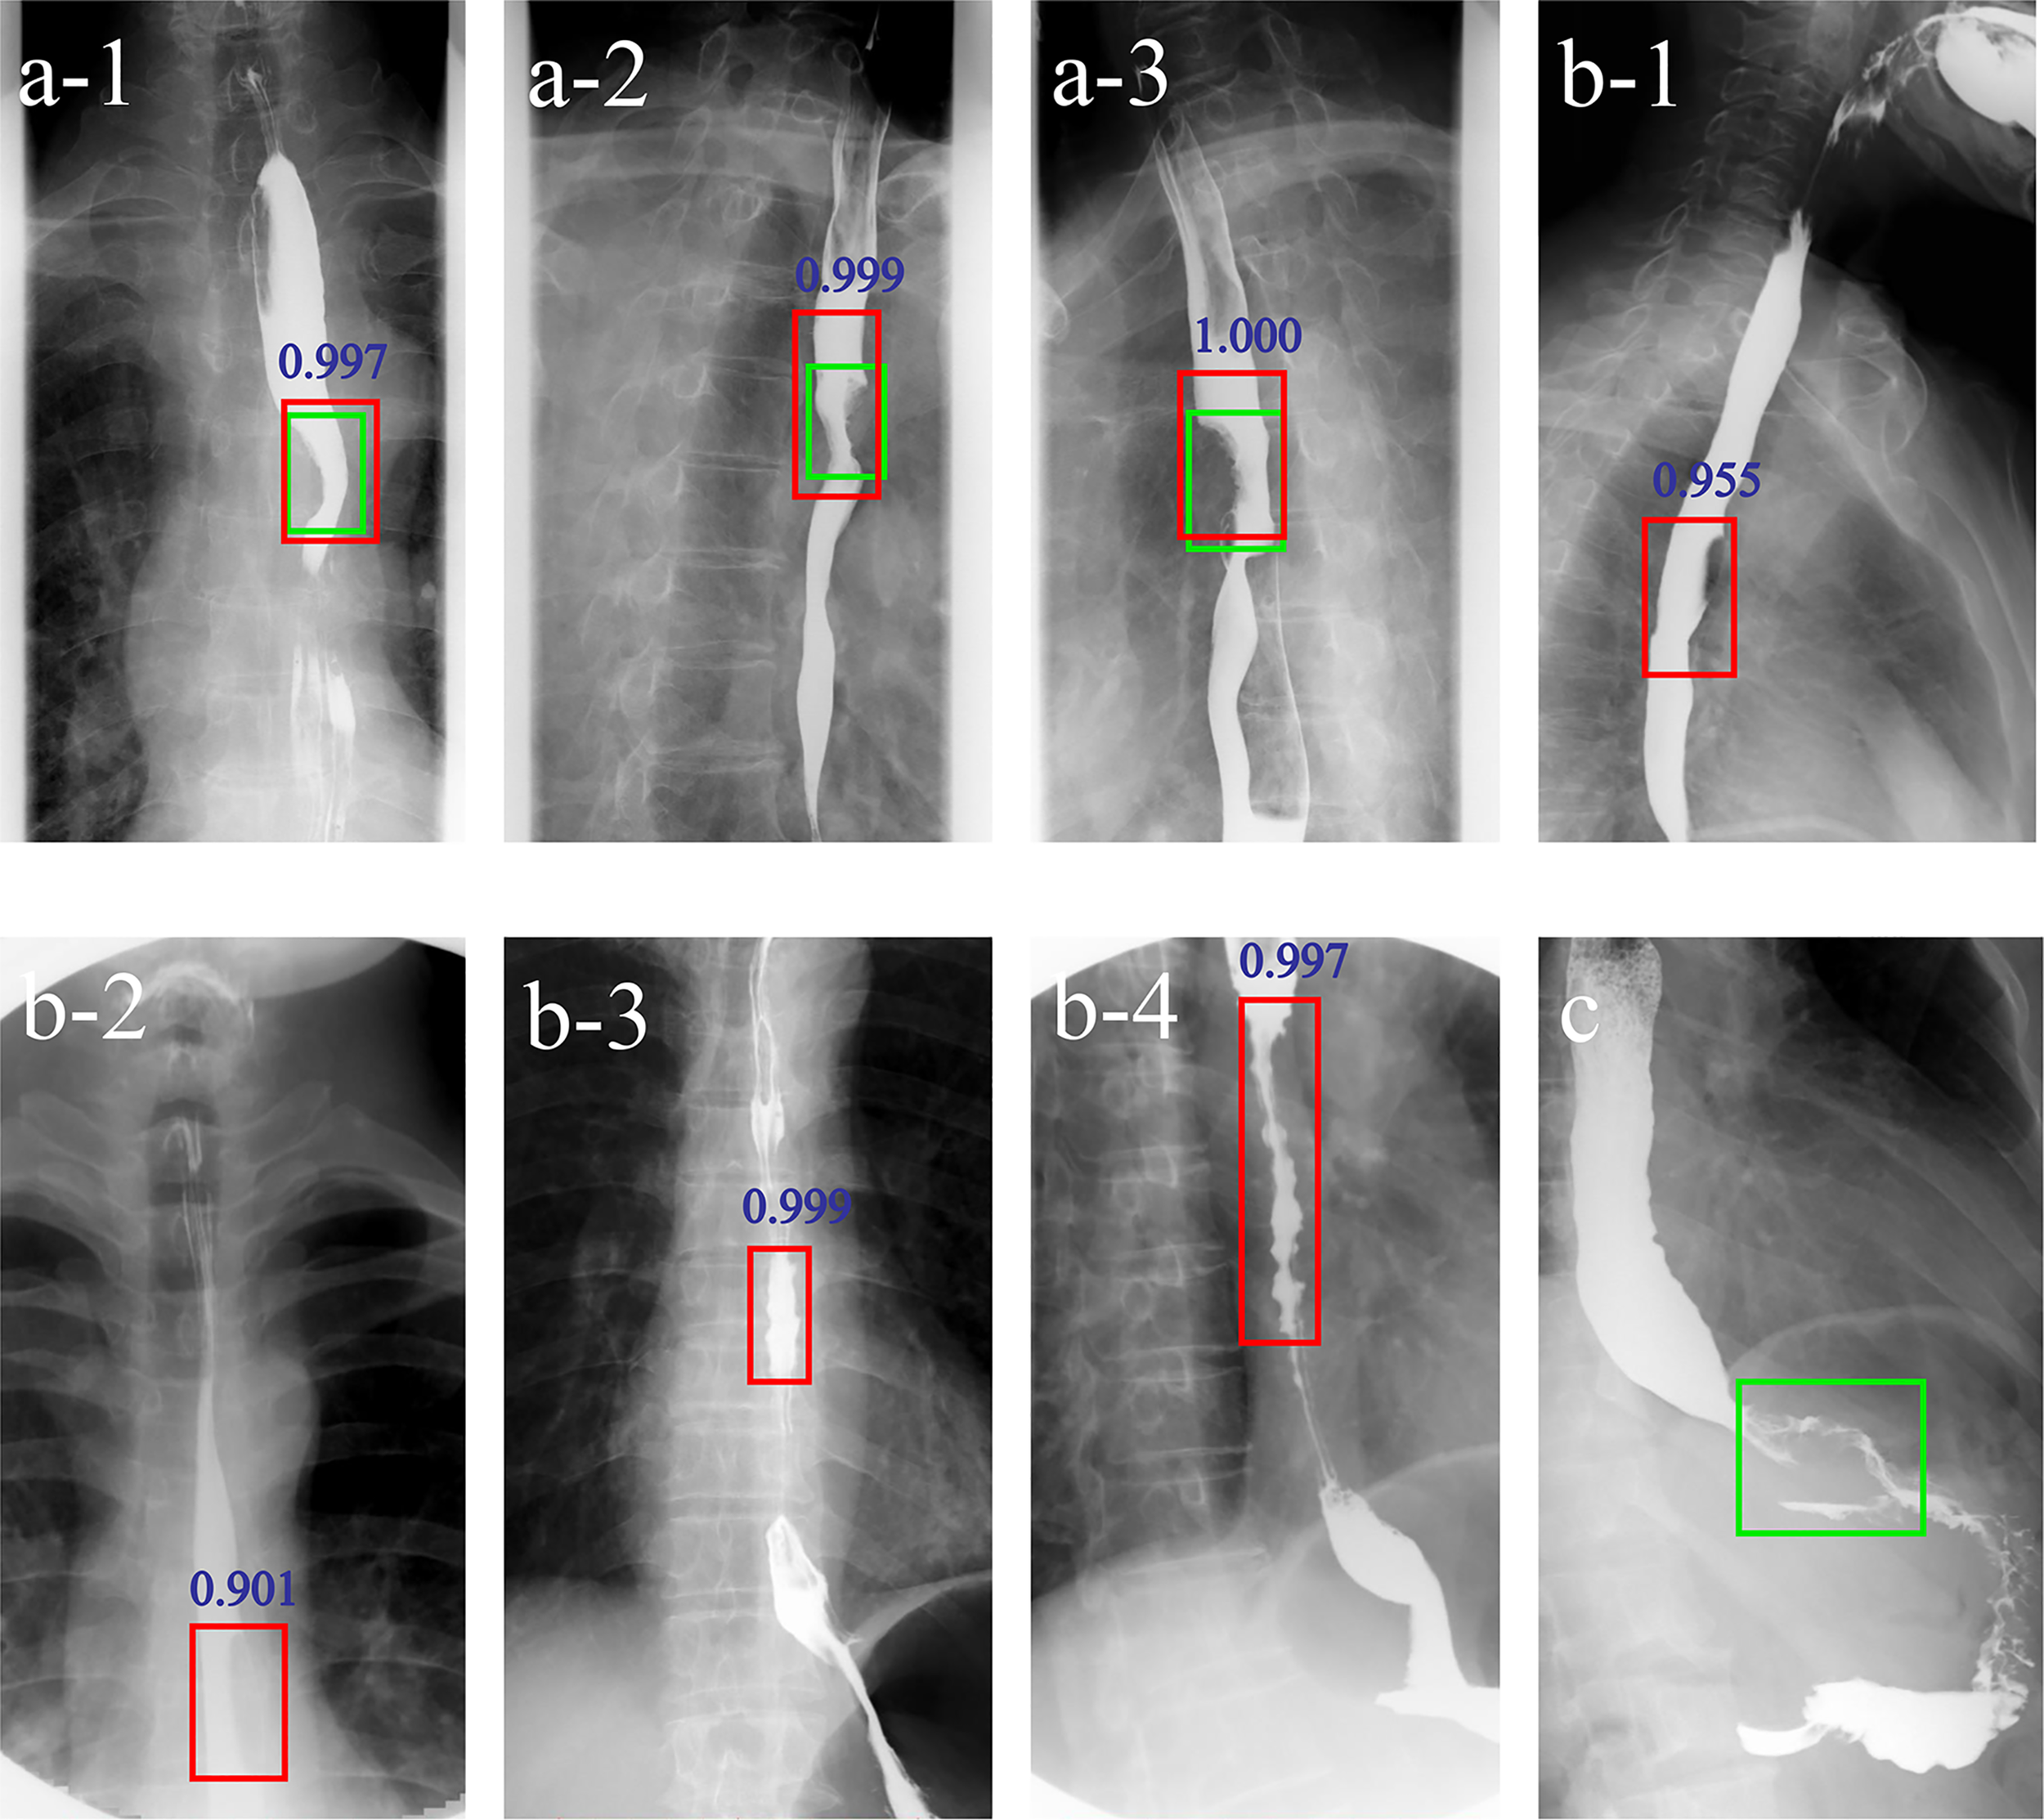

Applying the DLS alone, three false negative and six false positive cases were detected. For Reader1, with DLS aid 4/5 false negative cases were correctly classified into the positive group and 5/5 false positive cases were correctly classified into the negative group. For Reader2, with DLS aid 6/9 false negative cases were correctly classified into the positive group and 2/2 false positive cases were correctly classified into the negative group. Figure 4 shows examples of false negative and false positive barium esophagrams.

Figure 4

Examples of DLS-diagnosed images. The green boxes indicate the ground truth annotated by radiologists. The red boxes and blue numbers indicate the positioning boxes and probability values outputted by the DLS. A-1-A-3 are true positive cases. B-1-B-4 are false positive cases. (C) is a false negative case. A-1-3 represent three positions (anteroposterior, right anterior oblique, and left anterior oblique view) of barium esophagrams from a 71-year-old male esophageal cancer patient. A filling defect and eccentric stenosis in the middle of the esophagus can be noticed. B-1, B-2 represent misdiagnosis of esophageal cancer based on the false filling defect caused by gas. B-3, B-4 represent misdiagnosis of esophageal cancer based on tertiary waves (red boxes) in a 64- and a 78-year-old patient, respectively. (C) represents missed diagnosis of esophagogastric junction cancer. DLS, deep learning system.